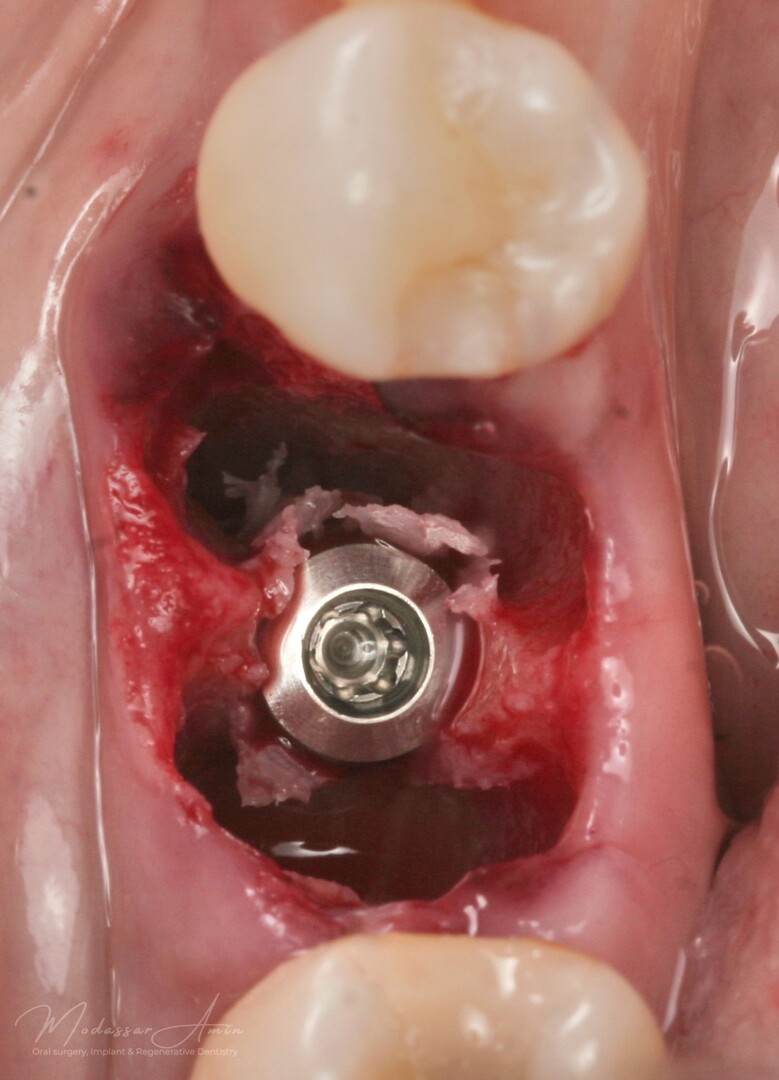

God primær stabilitet på 40+ ncm

SSA (Sealing Socket Abutment) + CTG (bindevevsgraft)